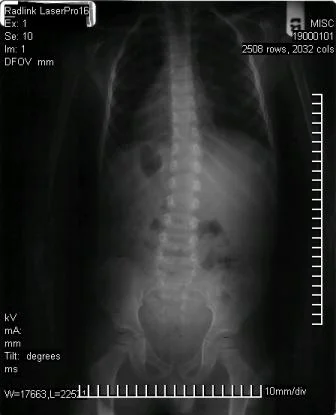

Before Corrective Care (manual short term adjusting)

After Corrective Care (manual short term adjusting)